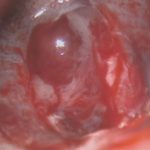

618

'25年4月

40代

小脳血管芽腫

頭蓋内腫瘍摘出術

No.’25_20 手術前1

No.’25_20 手術前2

No.’25_20 摘出 前

No.’25_20  摘出 中

No.’25_20 摘出 後